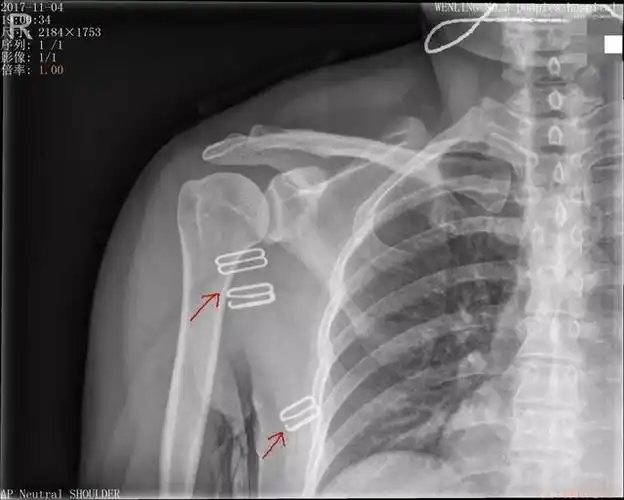

肩关节疼痛肩关节正侧位平片未见明显异常